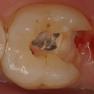

ancien amalgame

dépose des amalgames sous digue

nouveaux composites en place